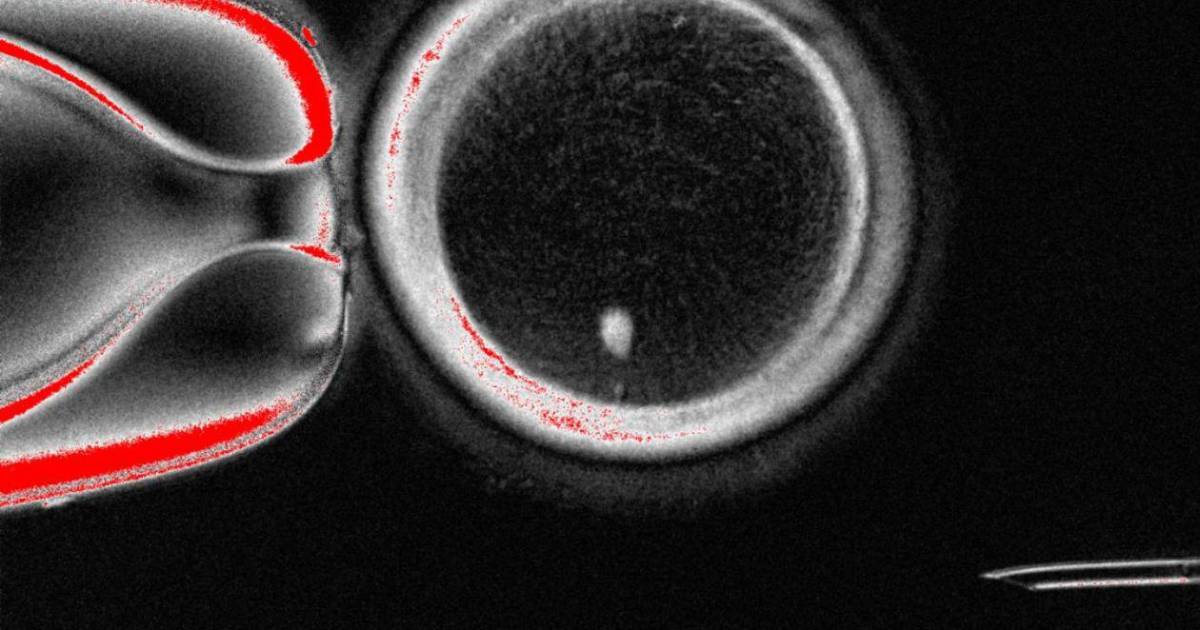

Una posible alternativa podría ser la transferencia nuclear de células somáticas, un proceso mediante el cual se trasplanta el núcleo de una de las células somáticas del propio paciente (como las células de la piel) a un óvulo donante al que se le ha extraído el núcleo, lo que permite que la célula se diferencie en un ovocito funcional.

El equipo extrajo el núcleo de las células somáticas de la piel y lo insertó en ovocitos de donantes a los que se les había extraído el núcleo.

Para resolver el problema del conjunto extra de cromosomas indujeron un proceso que denominaron "mitomeiosis", que imita la división celular natural y provoca que se descarte un conjunto de cromosomas, dejando un gameto funcional.

Aunque la segregación cromosómica se produjo de forma aleatoria, se conservaron una media de 23 cromosomas.

Los investigadores fertilizaron en laboratorio 82 ovocitos funcionales generados, de los que solo un 9 % se llegó a desarrollar durante seis días, hasta las fase de blastocito, cuando se paró el experimento, lo que coincide con el momento en que normalmente se transferirían al útero en un tratamiento de fecundación in vitro.